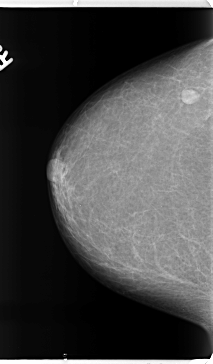

ics_version 1.0 filename B-3153-1 DATE_OF_STUDY 13 5 1998 PATIENT_AGE 69 FILM FILM_TYPE REGULAR DENSITY 1 DATE_DIGITIZED 21 4 1998 DIGITIZER LUMISYS LASER SEQUENCE LEFT_CC LINES 4688 PIXELS_PER_LINE 2720 BITS_PER_PIXEL 12 RESOLUTION 50 OVERLAY LEFT_MLO LINES 4688 PIXELS_PER_LINE 2776 BITS_PER_PIXEL 12 RESOLUTION 50 OVERLAY RIGHT_CC LINES 4728 PIXELS_PER_LINE 2760 BITS_PER_PIXEL 12 RESOLUTION 50 NON_OVERLAY RIGHT_MLO LINES 4736 PIXELS_PER_LINE 2872 BITS_PER_PIXEL 12 RESOLUTION 50 NON_OVERLAY |